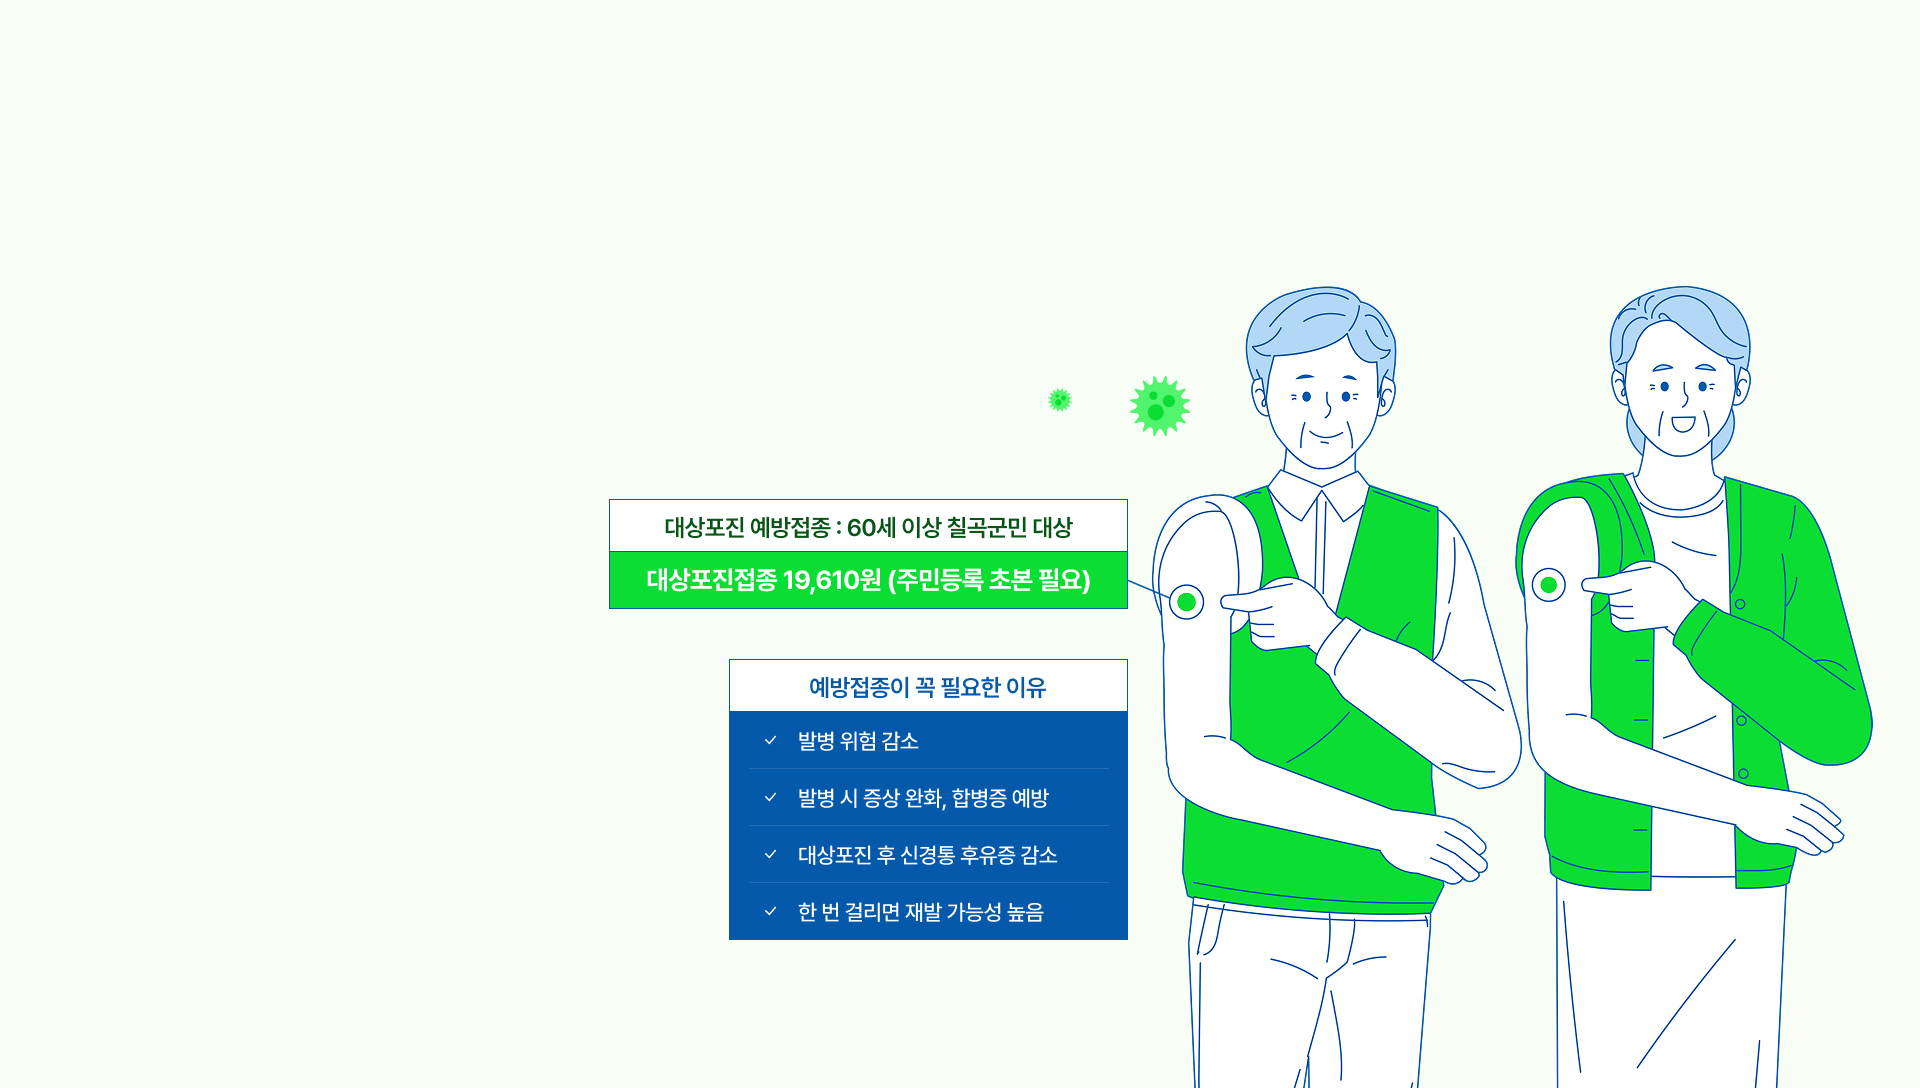

대상포진 예방접종

60세 이상 칠곡군민(1년 이상 거주자)

대상포진은 예방이 가장 중요합니다!

지금 건강을 지켜보세요.